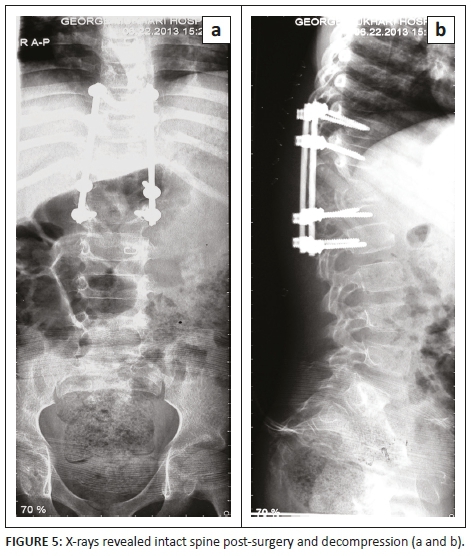

Non-operative treatment included a thoracic lumber spinal orthosis brace, analgesia and first-line tuberculosis treatment to prevent further collapse and back care. The patient's mother consented to operative management, which included spinal decompression and posterior instrumentation, with rods and screws, as well as a biopsy. The patient was neurologically intact post-surgery (Figure 5). The operation was successful.